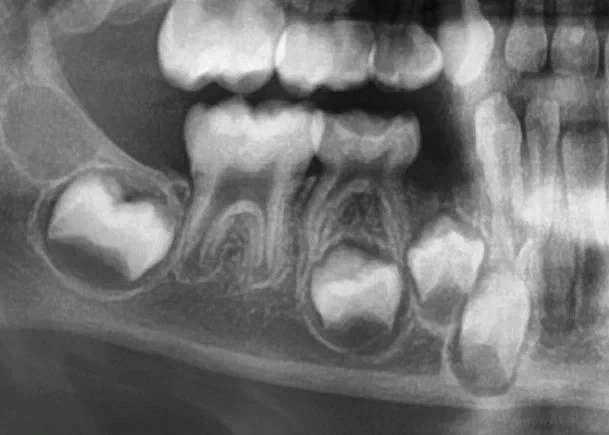

На этом рентгеновском снимке челюсти ребенка видно, как плотно в ней располагаются молочные зубы и зачатки постоянных.

В лучшем случае — может произойти нарушение развития ткани зуба, например, зуб прорежется с дефектами. В худшем — зачаток зуба может погибнуть. В крайне редких случаях инфекция распространяется еще глубже и появляется флегмона — острое гнойное воспаление, может начаться сепсис.